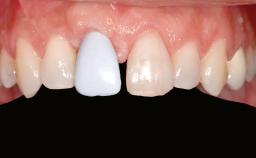

Ridge Preservation and Implant Placement for a Fixed Dental Prosthesis After a Car Accident

Prosthesis Type FDP

Patient's Esthetic Expectations Low Medium High

Lip Line No exposure of papillae Exposure of papillae Full exposure of mucosa margin